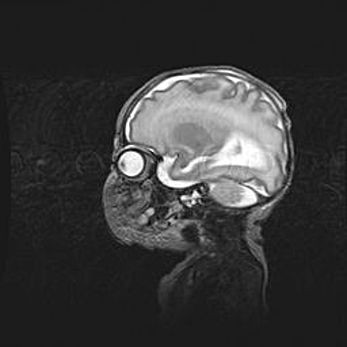

Аномалия Денди-Уокера. Признаки гипоплазии мозолистого тела.

Возраст: 5 месяцев 3 дня

Вес: 5550 г

Пол: мужской

Окружность головы: 39 см

Срок гестации: 40 недель

Аномалия Денди-Уокера – это порок развития головного мозга, для которого характерна триада симптомов: гипотрофия или аплазия червя мозжечка и/или полушарий мозжечка, расширение четвёртого желудочка с формированием ликворной кисты задней черепной ямки, гипертензионная гидроцефалия различной степени.

Гипоплазия мозолистого тела относится к дефектам внутриутробного этапа развития мозговой ткани, возникающим в процессе закладки структур головного мозга, что происходит на начальных этапах развития эмбриона.